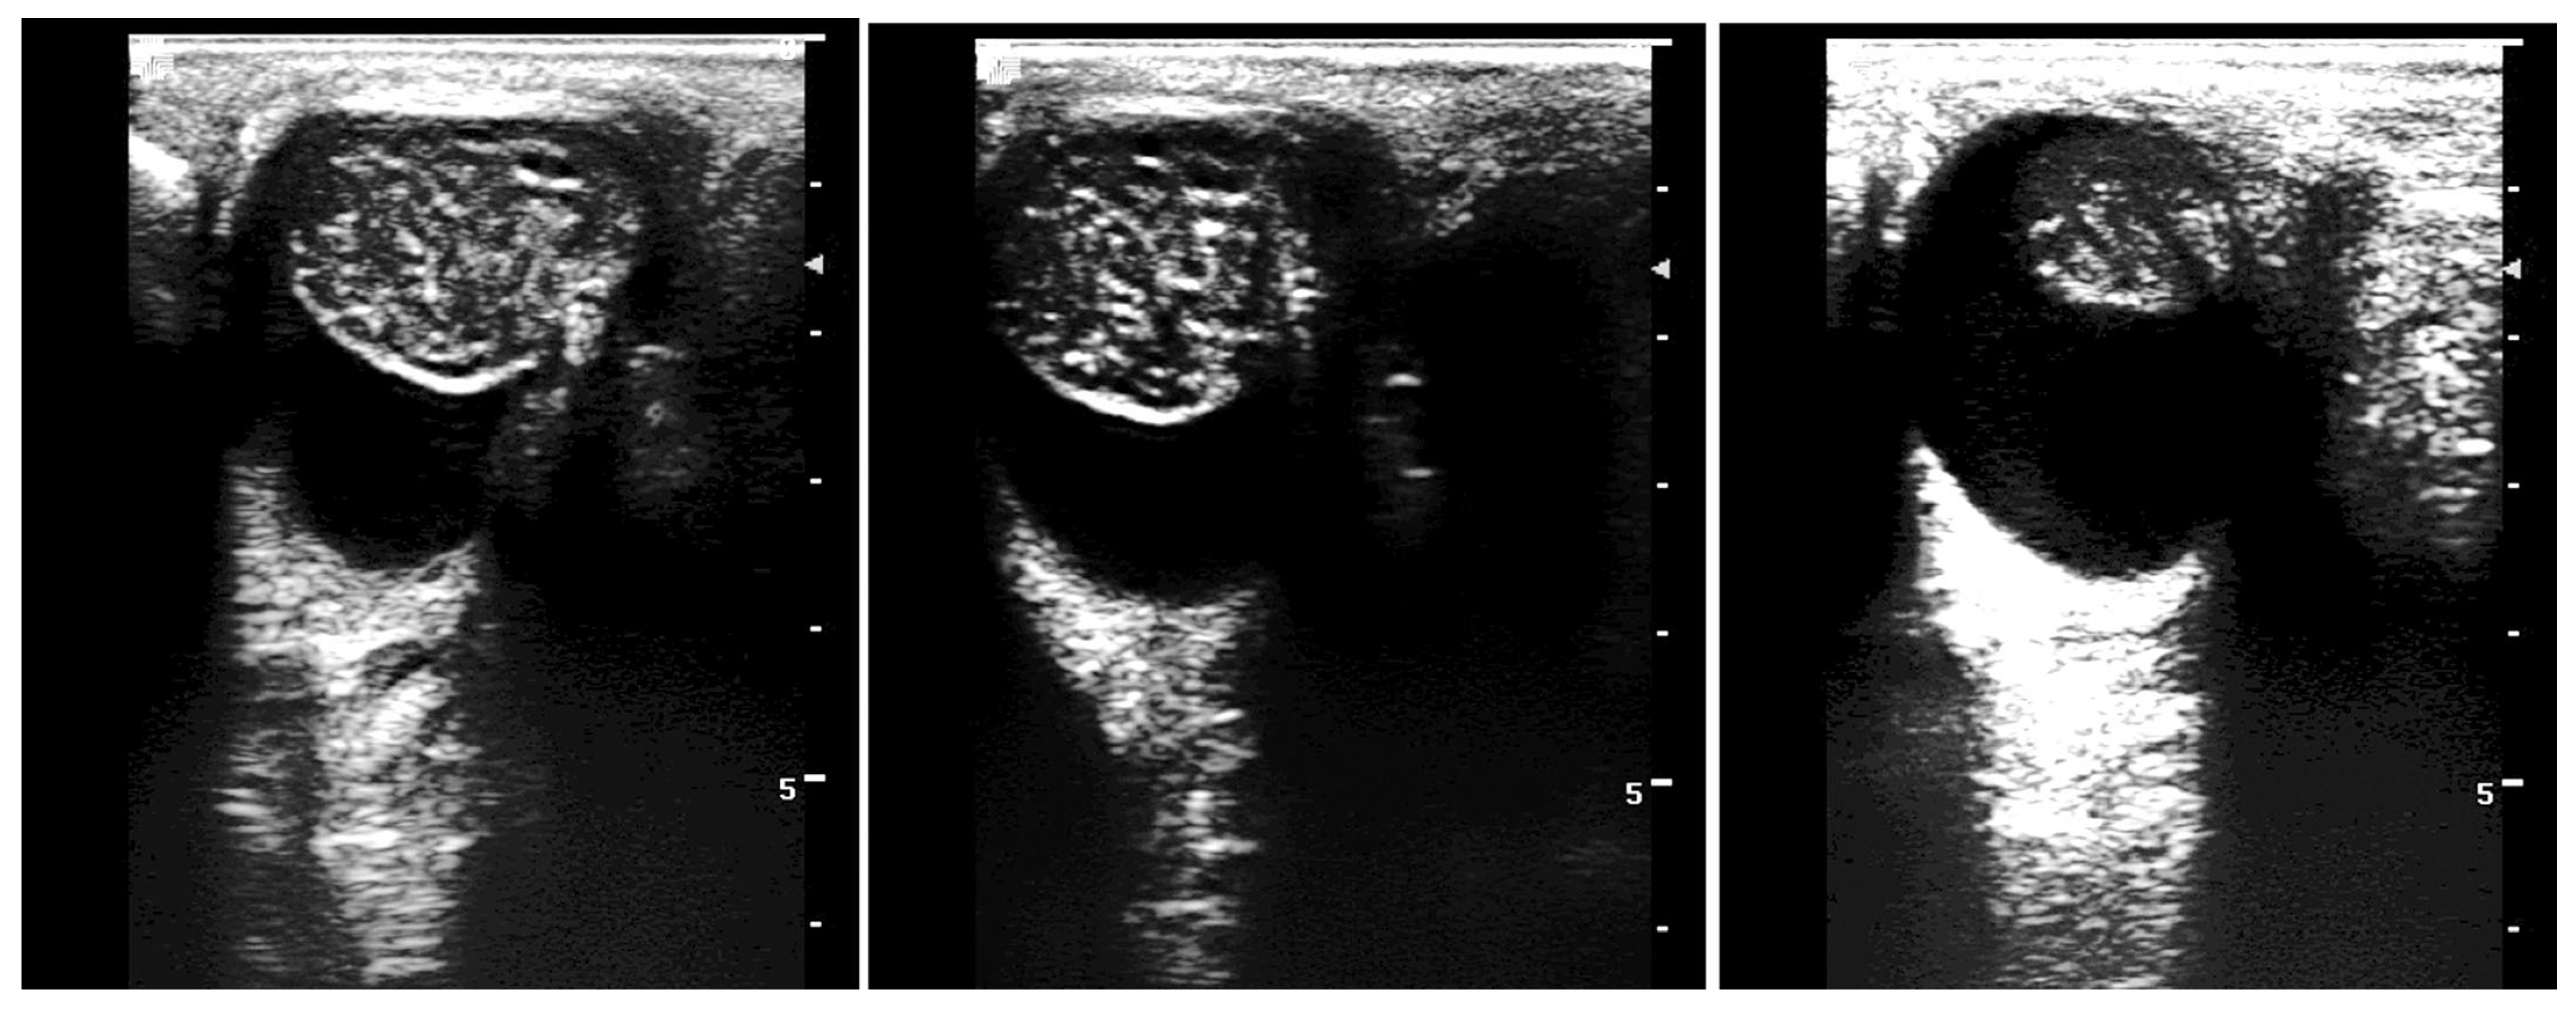

5.1. Hydrocele

5.2. Pyocele

5.3. Varicocele